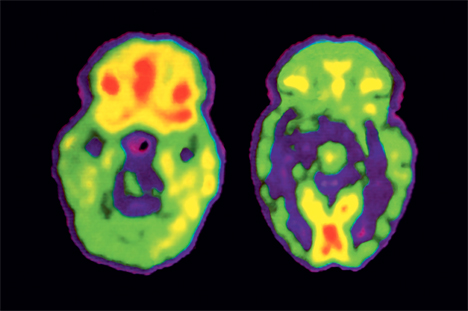

«Le système nerveux, qui pèse 2% du poids de notre corps mais consomme 25% de l’oxygène, est particulièrement vulnérable au stress oxydatif, poursuit Kim Do Cuénod. Nous avons pu observer un déficit du système antioxydant dans le cerveau des patients atteints de schizophrénie, soit par imagerie cérébrale, soit par une analyse du liquide céphalo-rachidien.» Ce travail est conduit dans le cadre d’une collaboration étroite avec le Centre d’imagerie biomédicale de l’EPFL, où sont conduites les mesures d’imagerie qui permettent entre autres d’observer la concentration d’antioxydants dans le cerveau animal et humain, ainsi que les connexions intracérébrales.

Un des facteurs à l’origine de la schizophrénie aurait donc dans certains cas une origine génétique qui empêcherait un contrôle de l’équilibre oxydatif du cerveau. Ce qui a des conséquences en cascade, comme, par exemple, une détérioration de la myéline, cette gaine isolante qui entoure les cellules nerveuses. Ce déficit perturbe la conductivité des fibres nerveuses et entraîne des problèmes de synchronisation entre les différentes parties du cerveau.